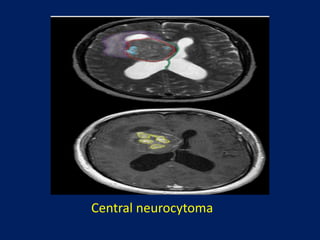

Central neurocytoma